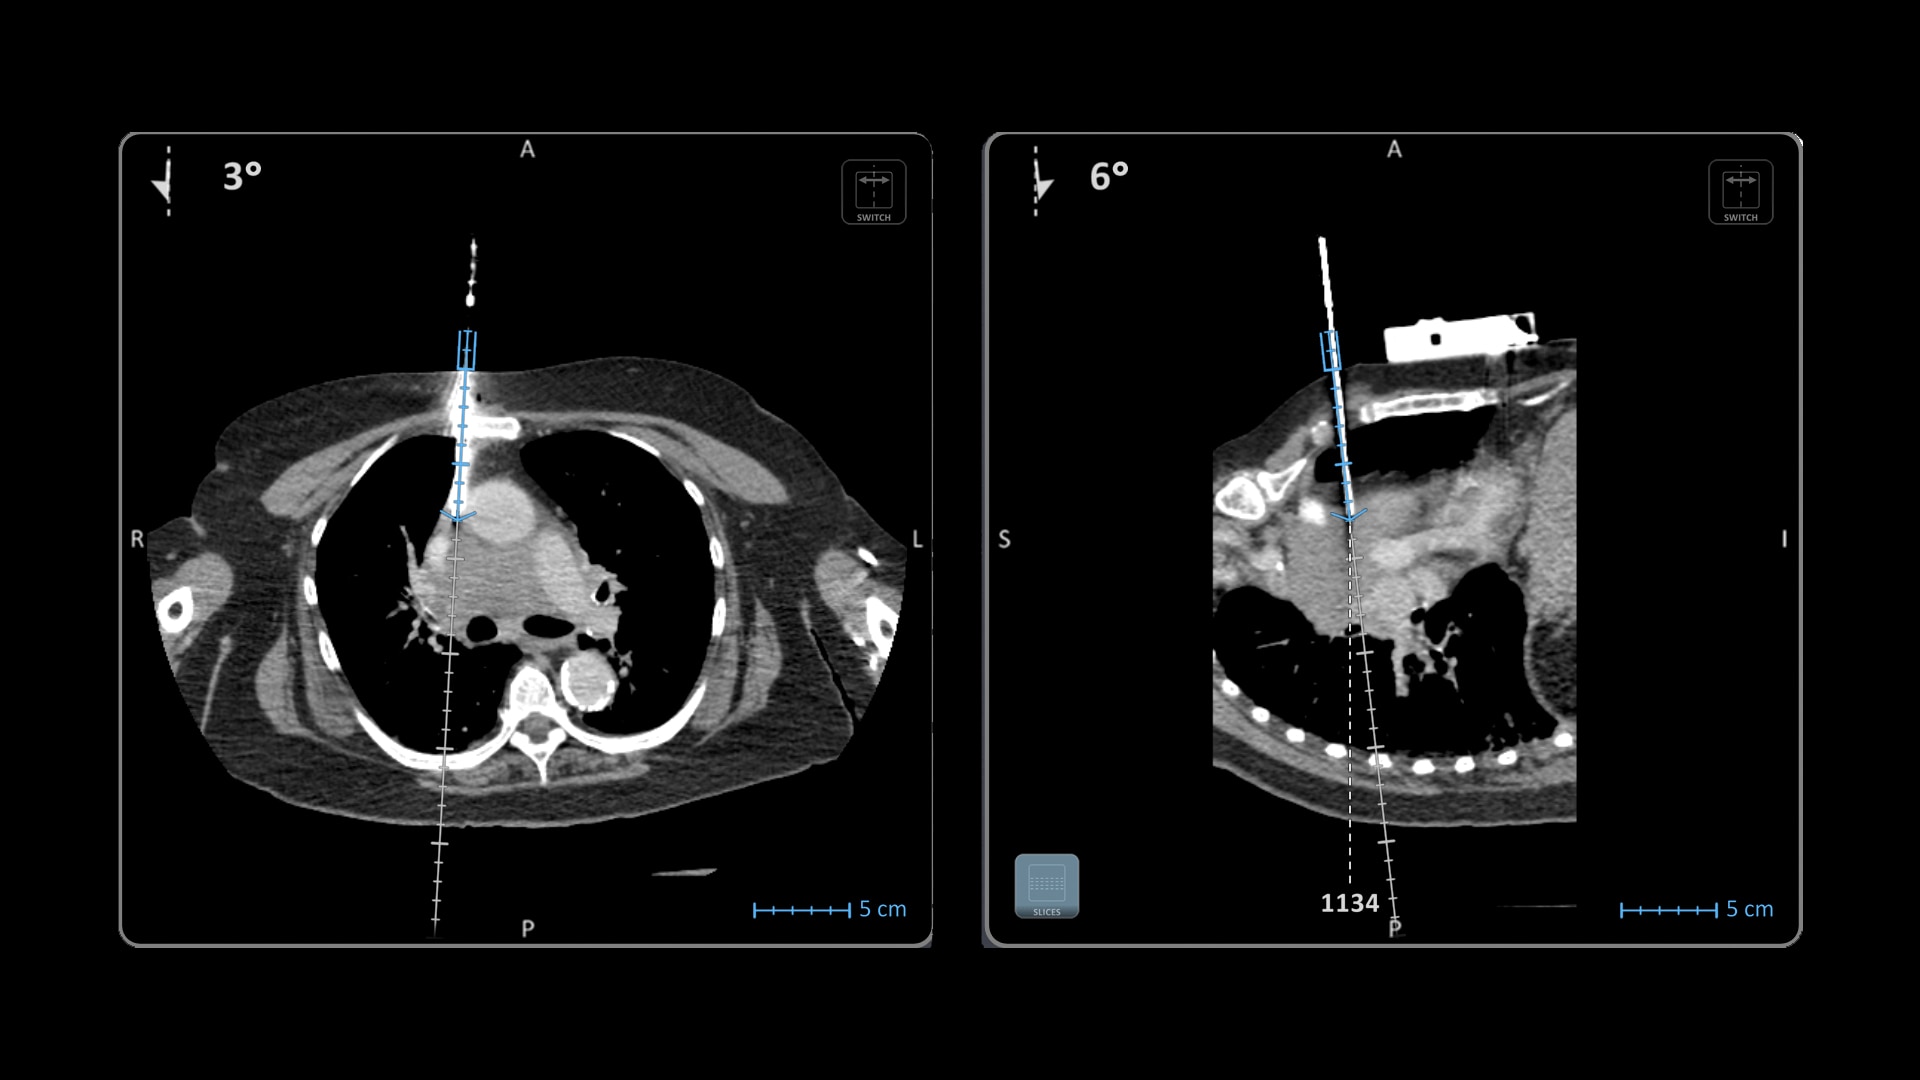

Versatility

Ideal to use with various percutaneous interventions² with various complexity